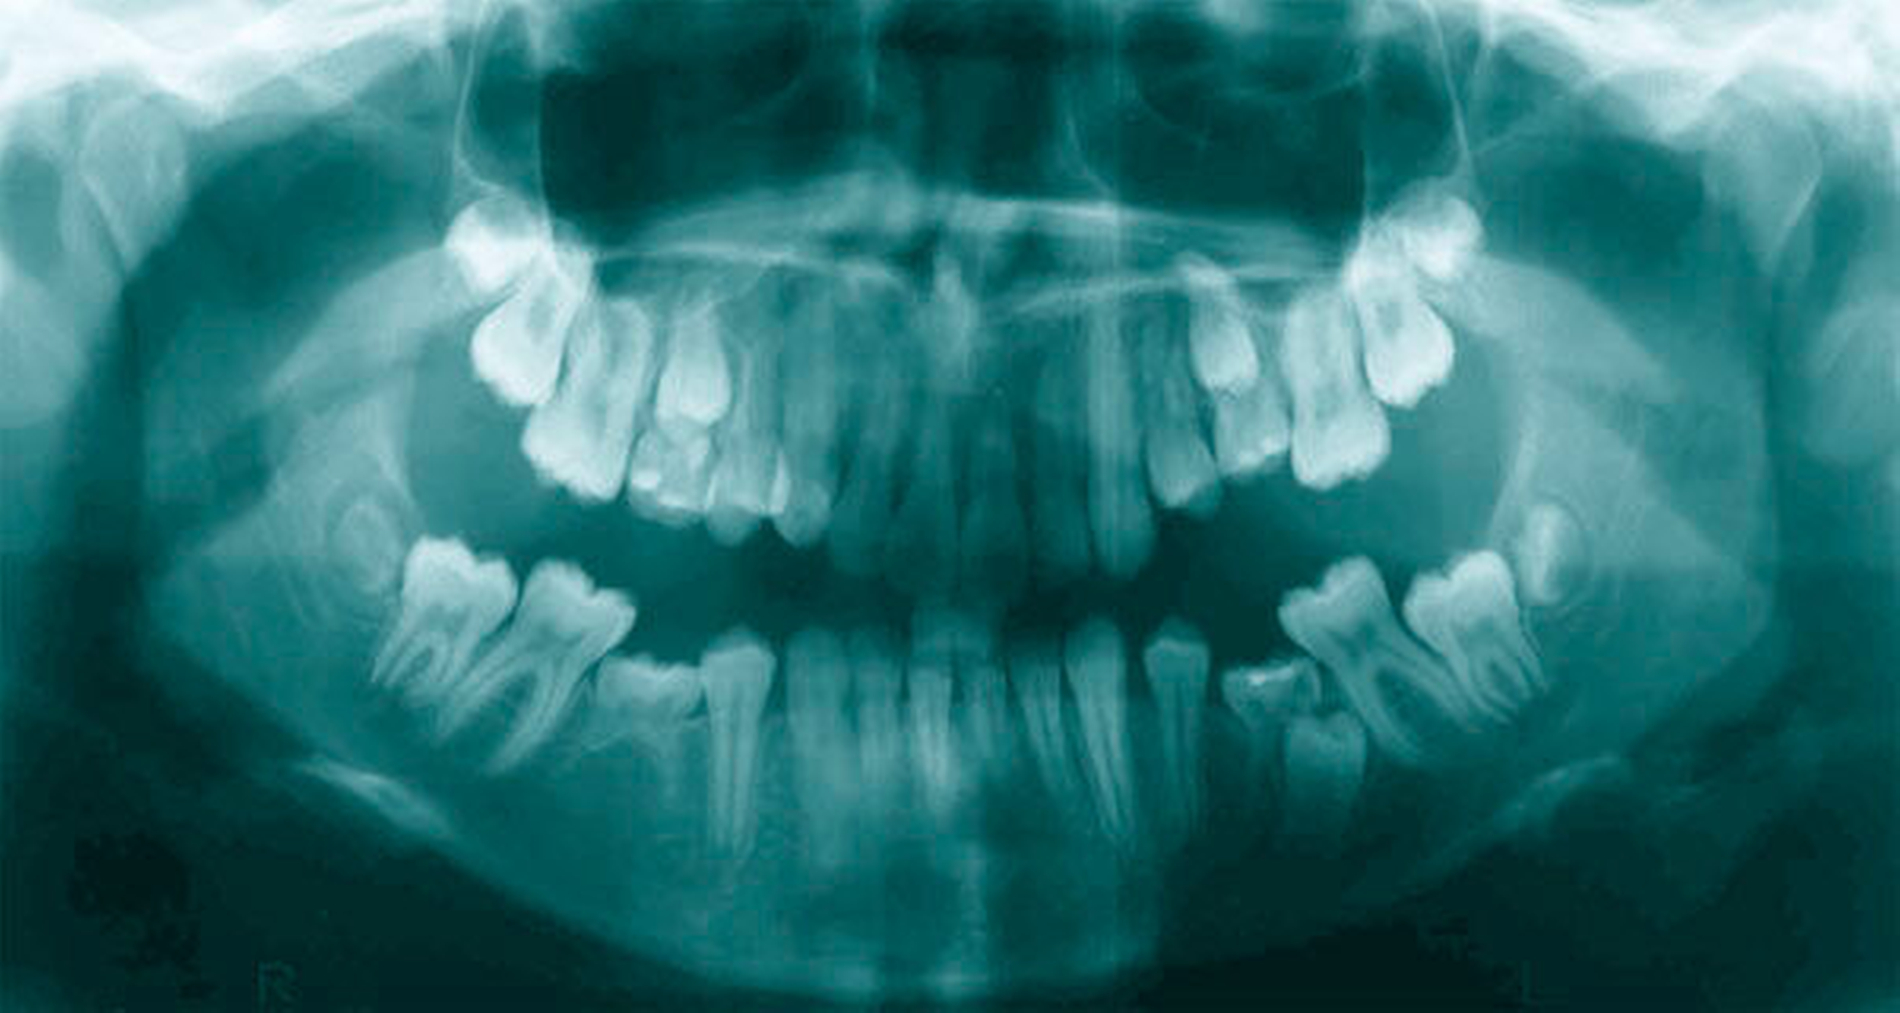

Wie bei den Molaren ist auch im Inzisivenbereich besonders auf Asymmetrien im Zahnwechsel zu achten. Neben vielen anderen Ursachen kann der Durchbruch der oberen Schneidezähne auch durch überzählige Zahnanlagen, beispielsweise einem Mesiodens zwischen den oberen mittleren Schneidezähnen, behindert werden. 85 Prozent aller überzähligen Zähne finden sich im Oberkiefer und dort überwiegend in der Region der mittleren Schneidezähne [Bodin, 1978]. Ein zeitlich deutlich verzögerter oder ausbleibender Durchbruch eines mittleren oberen Inzisivus kann ein Hinweis auf ein Durchbruchshindernis sein und sollte röntgenologisch abgeklärt werden (Abbildung 7)! Eine Aplasie des mittleren oberen Schneidezahns ist mit einer Prävalenz von 0,01–0,04 Prozent extrem selten [Polder, 2004]. Als letzte Zähne der ersten Wechselgebissperiode brechen die lateralen oberen Inzisiven im Alter von circa acht Jahren durch. Da diese Zähne nach den unteren Fünfern am zweithäufigsten nicht angelegt sind [Polder, 2004], sollte bei Milchzahnpersistenz beziehungsweise ausbleibendem Durchbruch differenzialdiagnostisch eine Übersichtsaufnahme angefertigt werden.